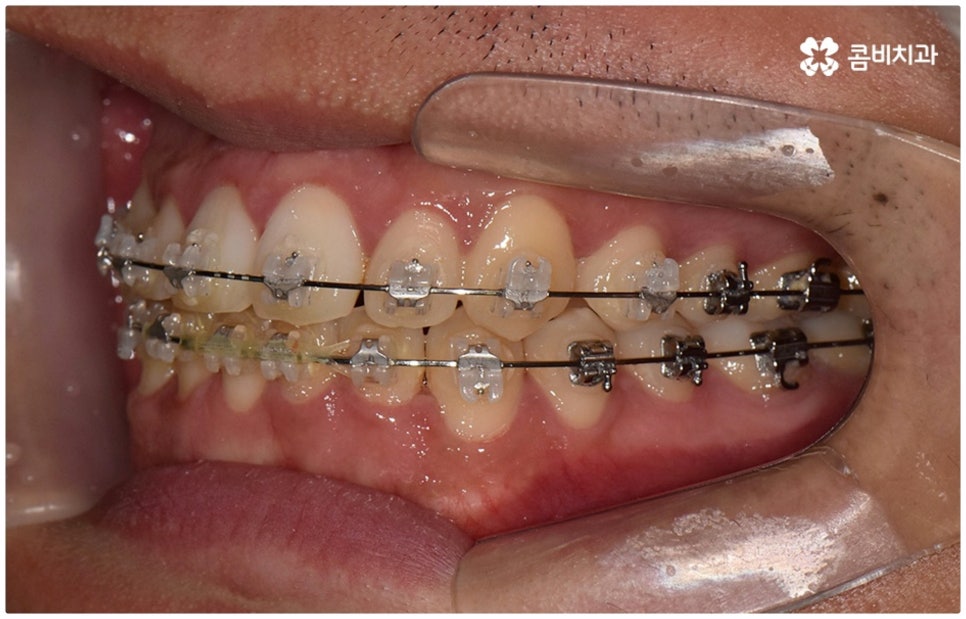

물론 교정 치료에 적기가 정해져 있는 것은 아니기 때문에 성인 이후 중장년 환자분들이라도 교정 치료가 불가능하지는 않으며 상황에 따라 비수술적인 방법으로도 얼마든지 불편함을 줄일 수 있는 경우가 있으니 정확하게 진단한 후 각자에게 맞는 교정 계획을 세워 무리하지 않게 치료를 진행하시길 바라고 있어요. 특히 턱관절과 관련된 부분을 개선하기 위해서는 양악 수술 밖에 방법이 없는 것이 아닌가 생각하셨던 분들이라면 먼저 치과에 내원하셔서 검진과 상담부터 진행해 보시면 마음의 부담을 덜 수 있어 좋을 거예요. 부정교합 3급 치열 (절단교합과 일부 반대교합이 병행되어 있음) 을 가지고 있는 성인분도 교정 치료를 통해 훨씬 자연스럽게 개선이 가능할 수 있으며, 관련 기술 개발 및 미니스크류 등 여러 장치의 발전을 통해 예전에는 적용이 어려웠던 케이스들도 이제는 교정 치료의 도움을 받을 수 있습니다.

위 사진은 이해를 돕기 위한 이미지이며, 환자의 동의하에 진행되었습니다.

전체 치료 기간은 약 18개월이 소요되었으며,

개인에 따라 출혈 및 부작용이 발생할 수 있고,

환자마다 치료 결과 및 기간이 상이할 수 있으므로,

정확한 치료 기간 및 치료 계획은

치과에서 상담을 받아보시길 권장 드립니다.